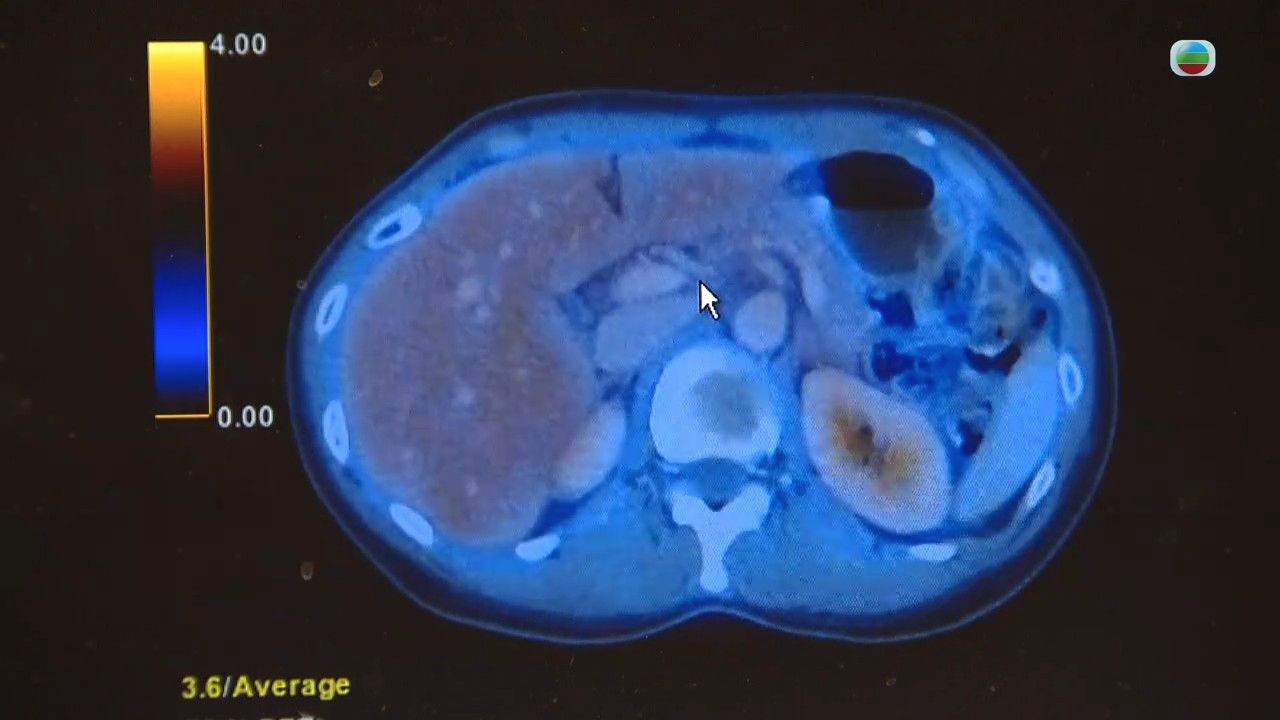

卵巢癌|卵巢癌是常見的婦女癌症,更在婦女癌症中排第六位。《最強生命線》中曾邀請專家講解卵巢癌治療方案。

臨床腫瘤科專科醫生潘智文指,卵巢癌在香港是常見癌症,45歲後屬卵巢癌常見發病年齡。如果年紀輕輕就患上卵巢癌,有機會是體內有遺傳性的癌症基因,約兩成卵巢癌患者帶有BRCA基因突變,而一半卵巢癌患者常見ARD基因突變。

卵巢癌治療方面,會根據腫瘤種類和期數制定治療方案:

• 早期:可先做手術,再做輔助性治療,例如化療、加減的標靶治療

• 三期或四期:先做化療、標靶藥等縮小腫瘤,再做手術